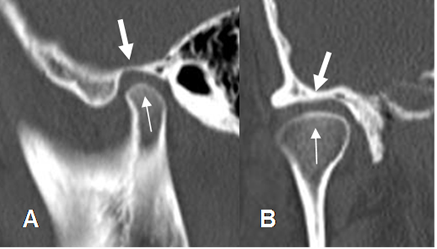

En los últimos años se ha utilizado la Tomografía axial computarizada (TAC) y las reconstrucciones tridimensionales para la valoración osea (Fig 3A y 3B) y en la actualidad la Resonancia magnética (RM) es la prueba de elección. Esta modalidad permite evaluar la morfología interna de la articulación y valorar la mecánica masticatoria. (1).

Fig 3A. ATM normal.

A: TAC reconstrucción sagital y B: TAC reconstrucción coronal. Articulación normal.

Cóndilo mandibular (Flecha delgada) y cavidad glenoidea. (Flecha gruesa).